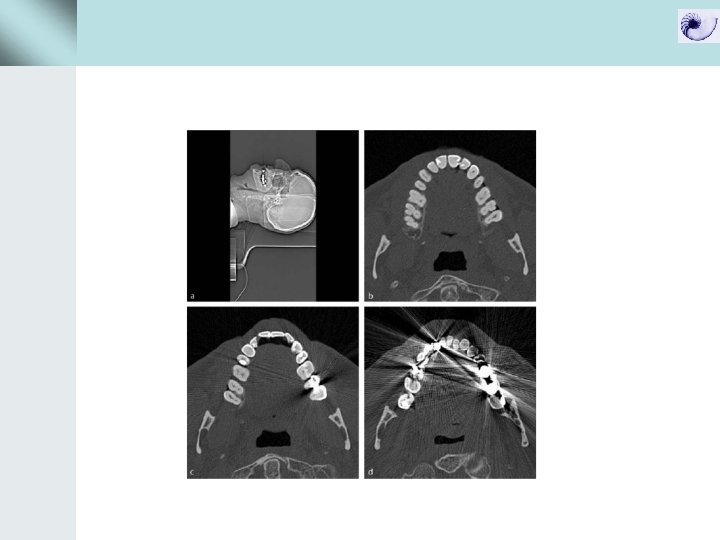

Ring artifacts